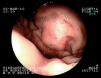

La repetición de la gastroscopia detecta en el pilar amigdalino izquierdo una lesión blanquecina ovalada, indicativa de la presencia de una úlcera revestida de fibrina (fig. 1A). En el fundus se visualiza una lesión amplia de aspecto angiomatoso de aproximadamente 3 cm de diámetro, sin coágulos ni vaso sangrante en su superficie (fig. 2). Se toman muestras para estudio anatomopatológico, el cual revela la existencia de una gastritis crónica activa, y para prueba de ureasa, positiva a los 10 min.

Figura 1. Úlcera a nivel de lecho amigdalar izquierdo, revestida de fibrina (A)y sin la misma (B).